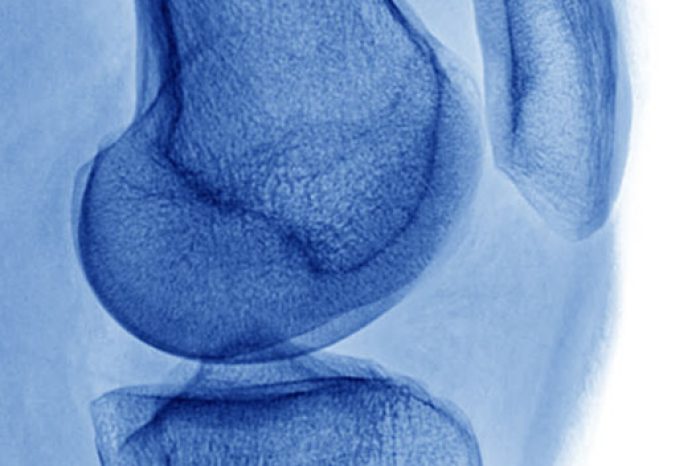

The diagnosis is primarily clinical, characterized by activity-related anterior knee pain and tenderness at the lower pole of the patella (Malliaras et al, 2015; Theodorou et al, 2023). The hallmark features are pain localized to the inferior pole of the patella and load-related pain that increases with demand on the knee extensors, particularly in activities that store and release energy in the patellar tendon.

Imaging (MRI or ultrasound) may show: